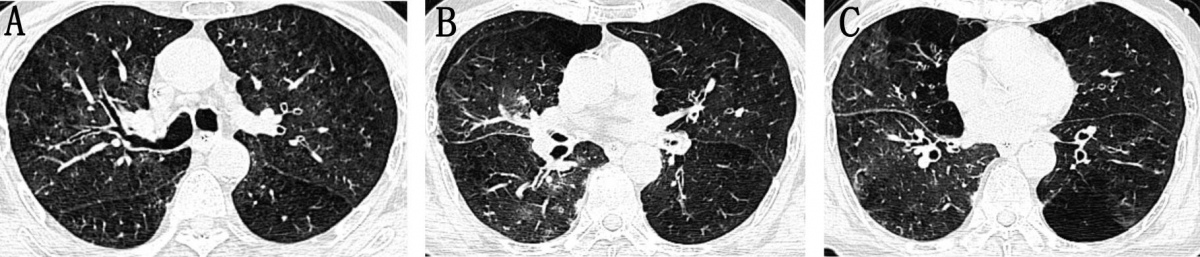

爆发型COPD-IPA早期的胸部CT表现

图像来自一位77岁男性COPD-IPA患者,因“咳嗽、咳痰、呼吸困难加重1天”入院。尽管及时给予抗真菌治疗,患者仍出现严重呼吸及循环衰竭,最终死亡。CT图像仅见双侧支气管壁增厚,伴周围磨玻璃影及树芽征。由于CT表现常缺乏特征性征象,增加了初始诊断的难度。